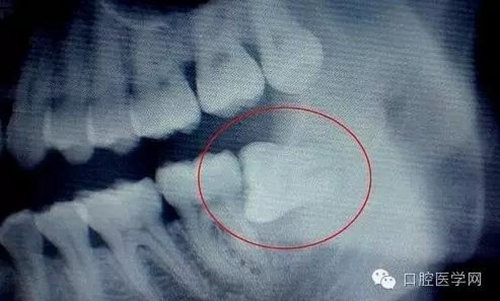

(3)第二磨牙齲壞:向前傾斜的阻生智齒,因經(jīng)常在鄰牙間積存食物,易發(fā)生鄰牙(下頜第二磨牙)齲壞。

3.jpg